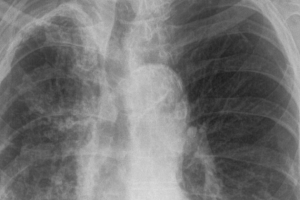

Tuberkuloza je bolest koja se danas dosta lako dijagnosticira. Važno je uzeti dobru anamnezu i obaviti pregled pacijenta, načiniti laboratorijske nalaze i RTG...